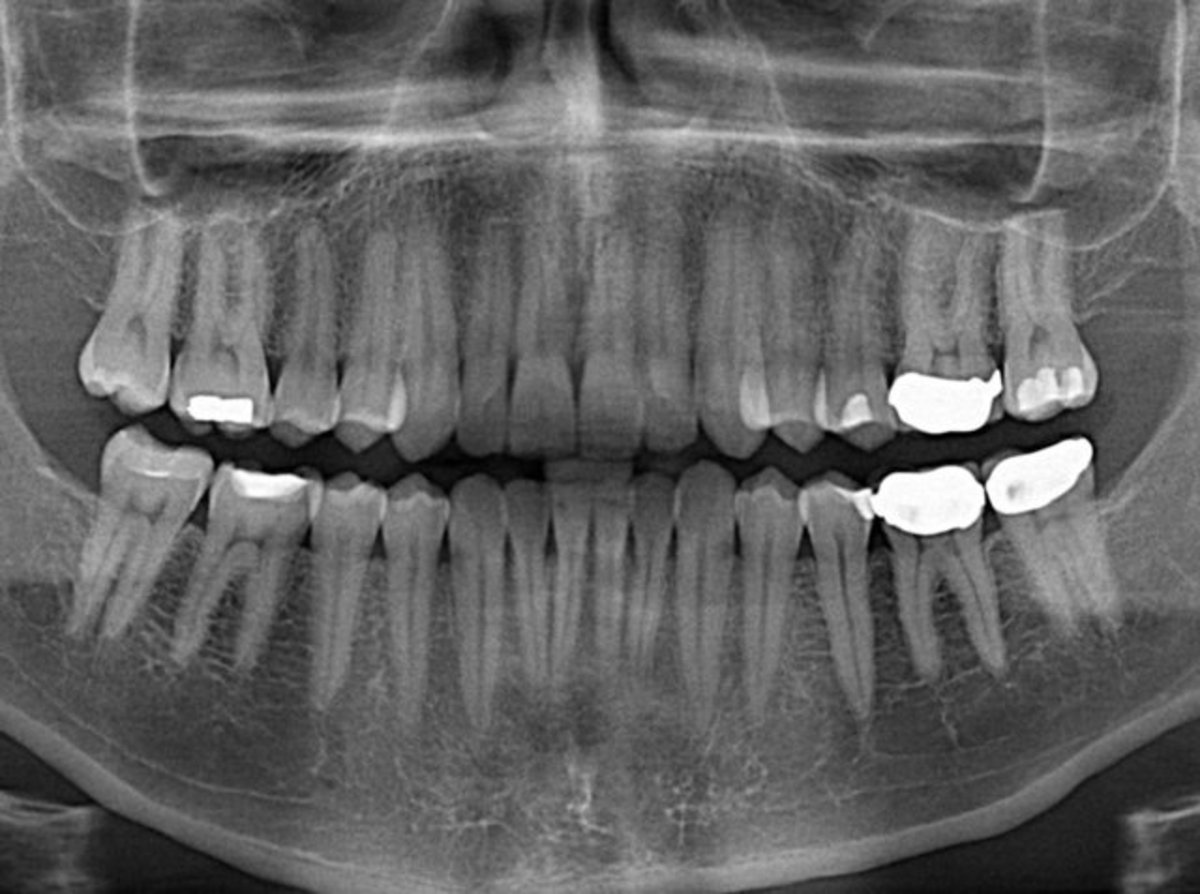

در این مطالعه که به سرپرستی دکتر رضا ملکزاده، استاد ممتاز دانشگاه علوم پزشکی تهران و پراستنادترین دانشمند علوم پزشکی ایران در بستر مطالعه کوهورت – بزرگترین مطالعه آیندهنگر خاورمیانه که از سال ۸۳ تاکنون، بیش از ۵۰ هزار ایرانی ۴۰ تا ۷۵ سال را با هدف بررسی عوامل خطر سرطانها و ساير بيماريهاي مزمن در شمال شرق ايران (استان گلستان) مورد بررسی و پیگیری قرار داده است – تعداد دفعات مسواک زدن، استفاده از دندان مصنوعی و پروتز دندان بر اساس خوداظهاری شرکتکنندگان و نیز وضعیت سلامت دندان آنها شامل دندانهای از دست رفته، فاسد، خالی و پر شده، توسط پزشکان آموزش دیده مورد بررسی قرار گرفتند.

وی اظهار داشته است که حتی شیوع پوسیدگی دندان در جهان در مقایسه با میگرن و آسم بیشتر است و بر اساس آخرین پیمایشهای انجام شده در میان افراد ۳۵ تا ۴۴ سال، به طور متوسط حدود ۳ دندان پر شده و ۶ دندان کشیده شده و ۴ دندان پوسیده وجود دارد. همچنین آمار دندانهای پوسیده در میان کودکان ایران، صعودی بوده است که این مساله هزینههای زیادی را برای درمان نیاز دارد.